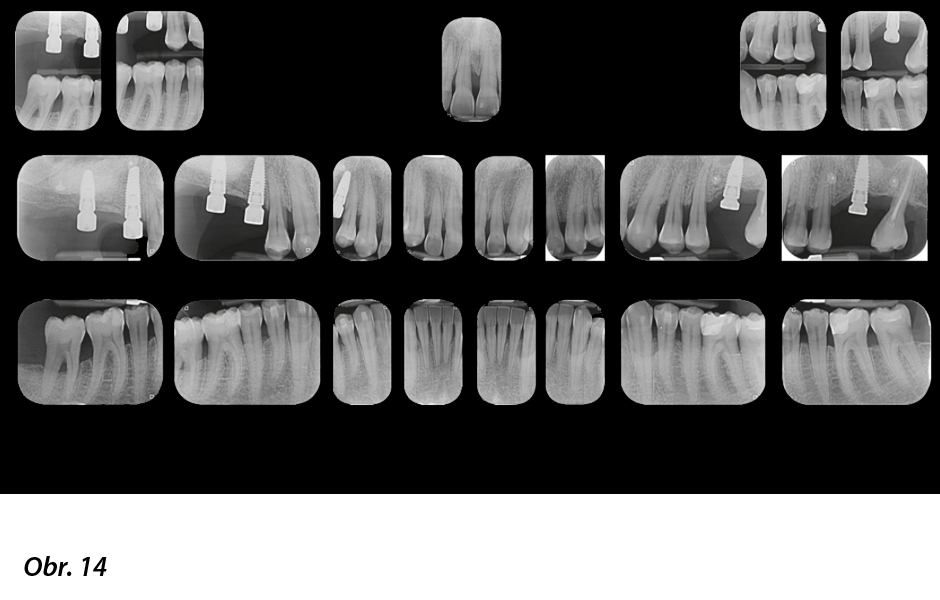

Posun byl o 50 % pomalejší, než je obvyklé, aby byly použity jen slabé síly s ohledem na maximální šetrnost k oslabenému závěsnému aparátu zubů. Ke korekci rozestoupených řezáků a zmenšení mezizubních prostor (obr. 14) byla použita první sada 22 alignerů. Pak byla provedena zdokonalovací fáze za použití 11 alignerů, jejímž cílem bylo zlepšit konečné uspořádání zubů a výslednou interkuspidaci. Výměna alignerů byla stanovena na každých 7 dní. Celková doba léčby byla 15 měsíců (obr. 15–21).

RTG snímky celých úst: 60% úbytek kosti (vertikálně i horizontálně)

RTG snímky celých úst na konci první sady alignerů